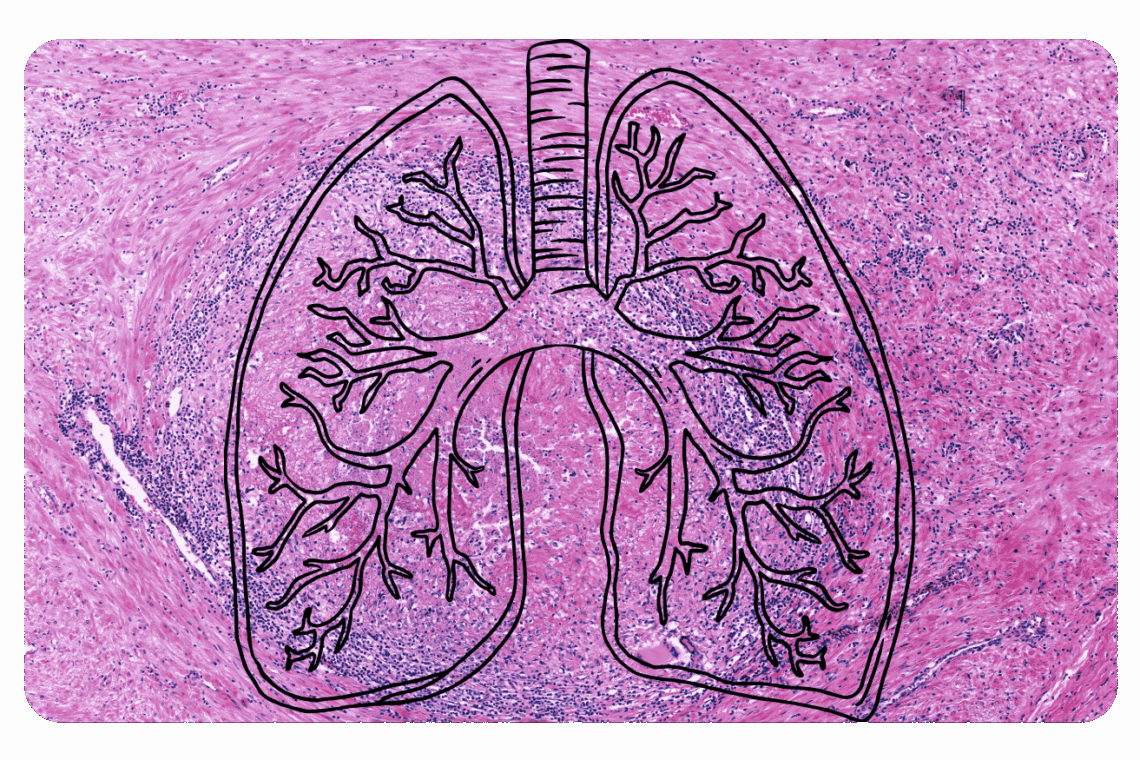

Maladies pulmonaires interstitielles : causes, symptômes et traitements

Les maladies pulmonaires interstitielles (MPI) constituent un groupe hétérogène de pathologies qui affectent principalement le tissu interstitiel pulmonaire - l'espace situé entre les alvéoles et les vaisseaux sanguins. Ces affections se caractérisent par une inflammation et/ou une fibrose progressive, entraînant une altération des échanges gazeux et une diminution de la fonction respiratoire.